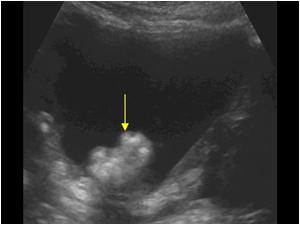

Mesanedeki Kitlenin Ultrason Görüntüsü

Mesanede kitle çoğu zaman herhangi bir belirti vermez ve genellikle başka nedenlerden dolayı yapılan ultrason gibi görüntüleme yöntemleri sırasında fark edilir. Ancak, idrarda kanama, ağrı, sık idrara çıkma gibi belirtiler görülebilir. Bu tür bir durum olduğunda ilk yapılacak iş ultrason incelemesidir.